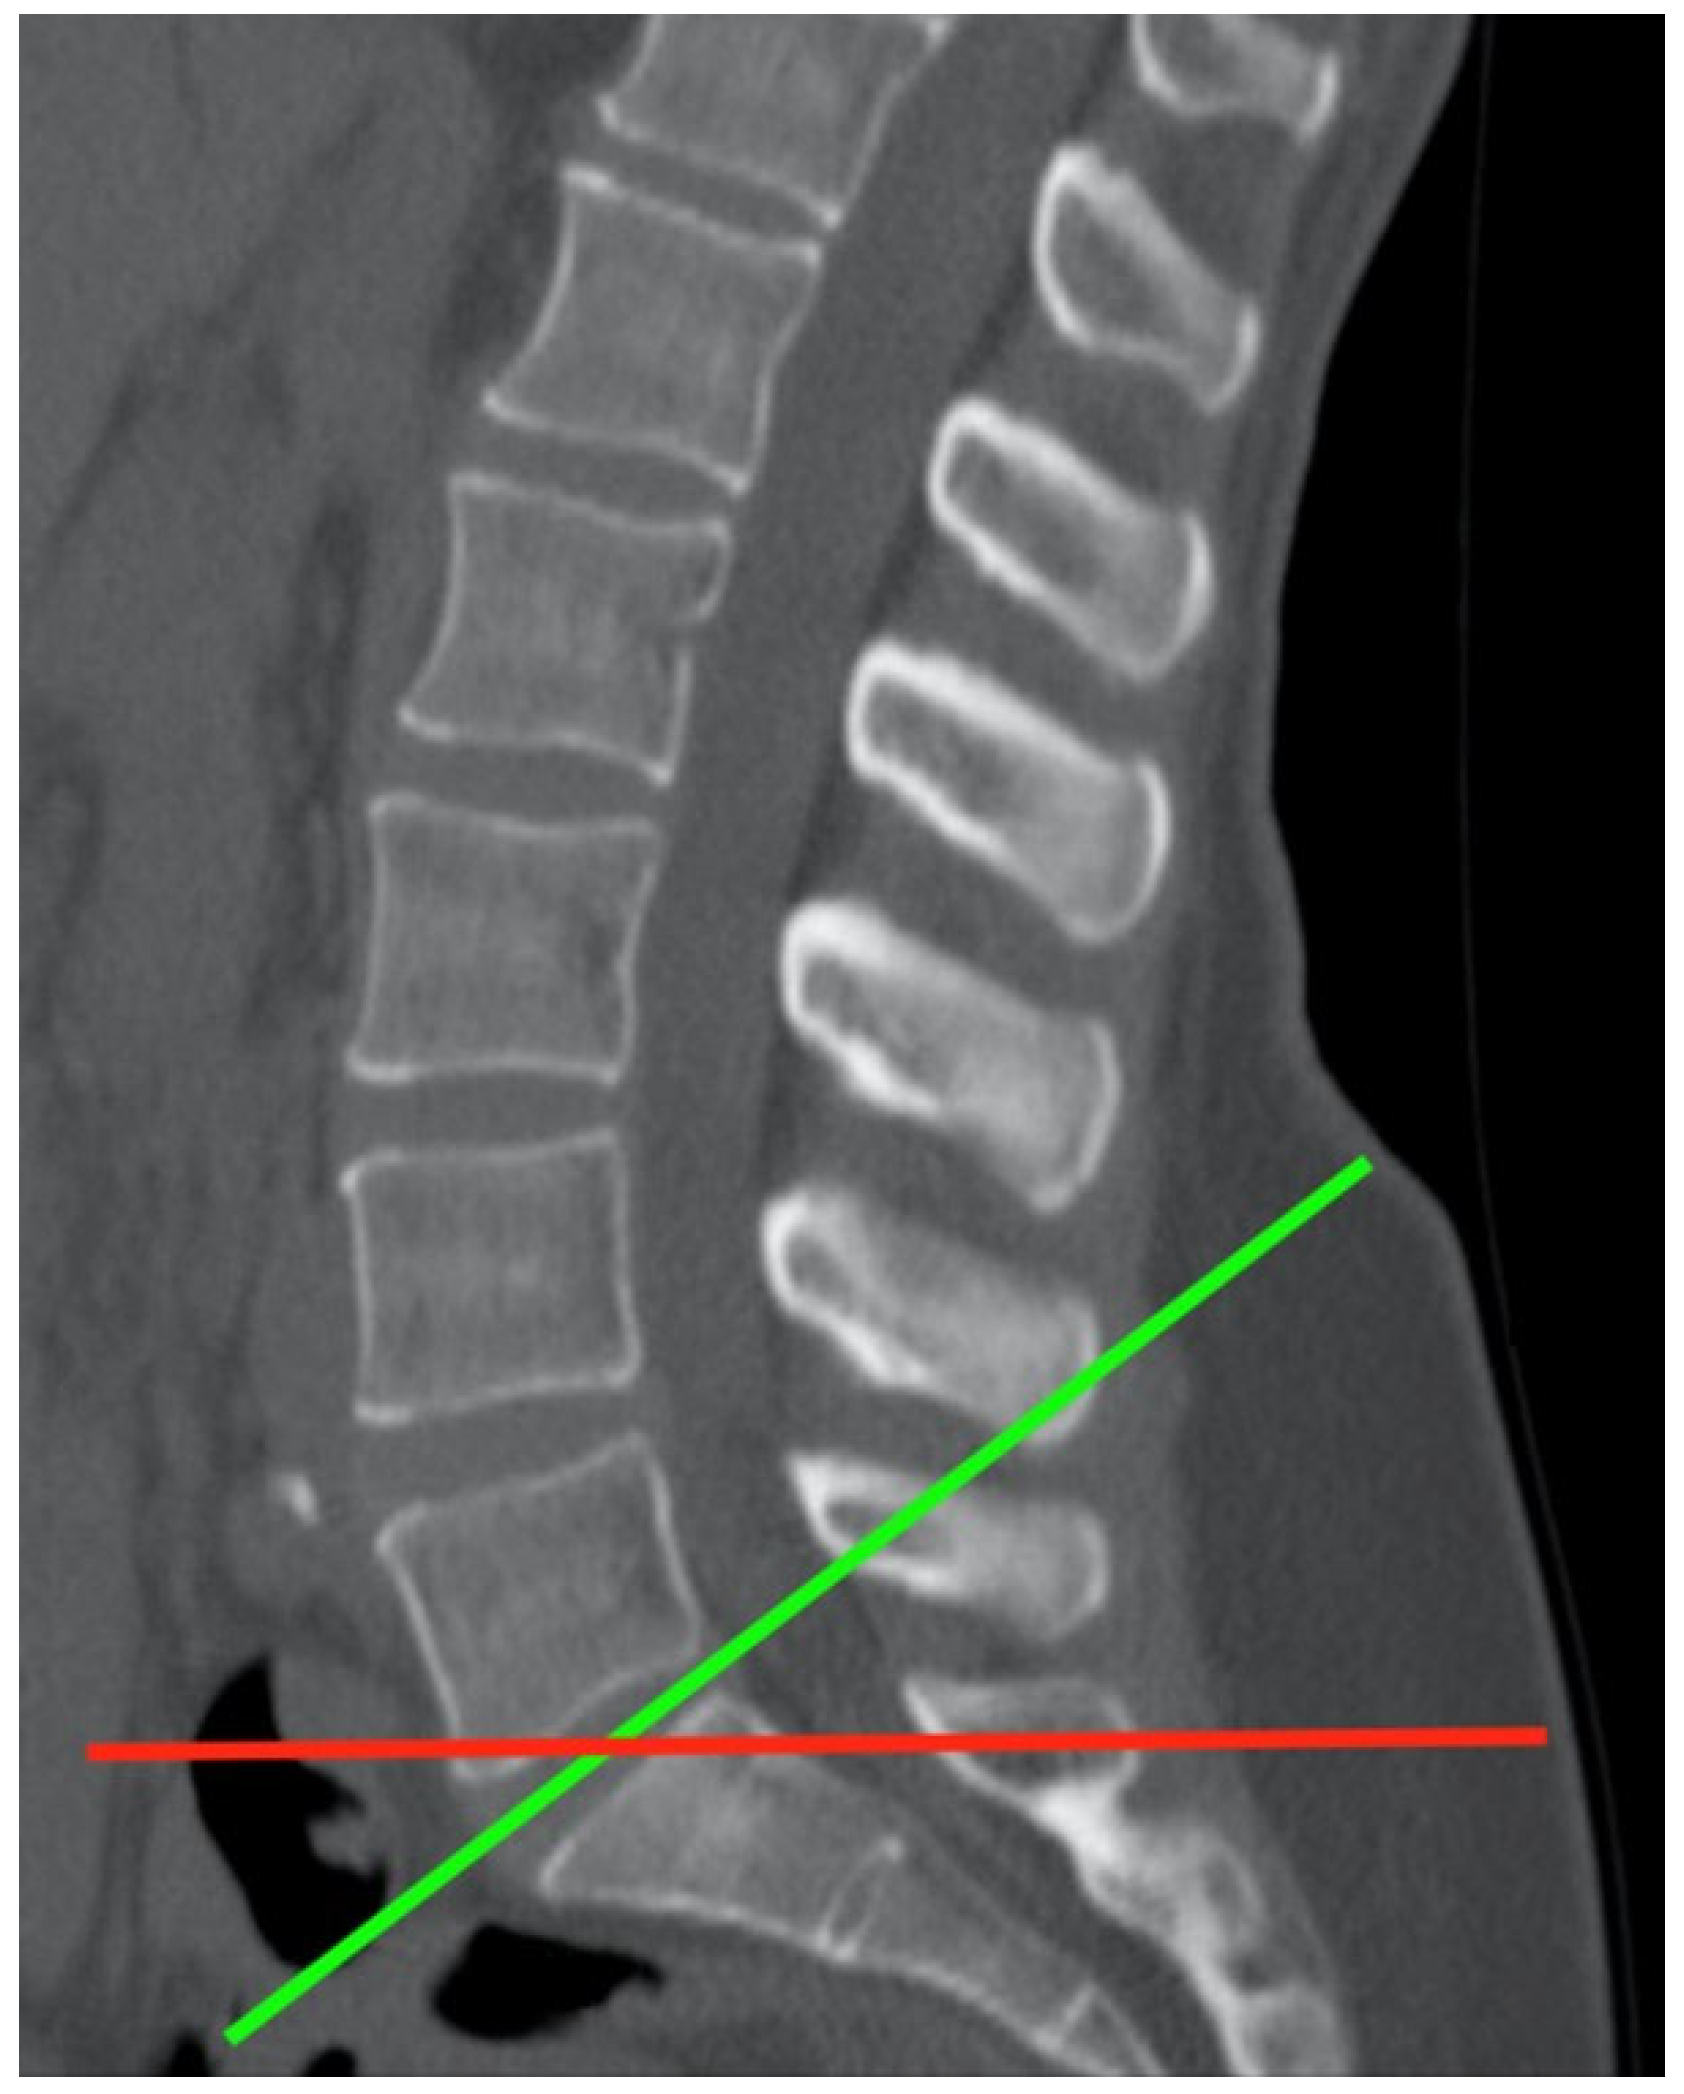

2.2. CT Imaging Research Methodology